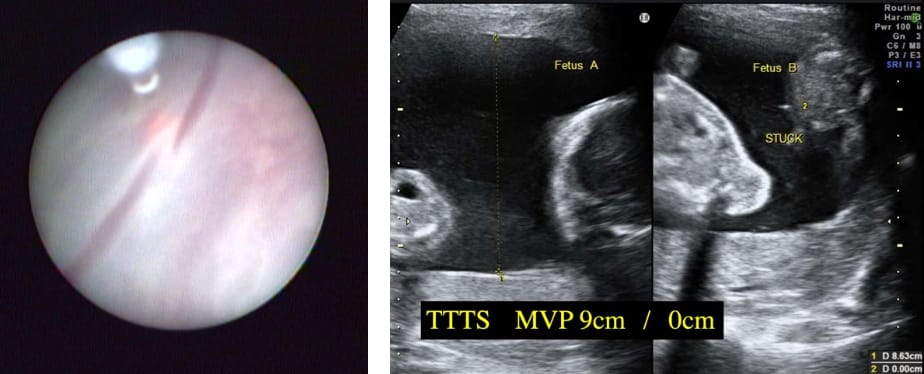

TTTS(双胎間輸血症候群)

双胎間輸血症候群(twin-to-twin transfusion syndrome : TTTS)は、一卵性の双子の中でも一つの胎盤を二人の胎児で共有するタイプ(一絨毛膜双胎)の5-10%に起こる病気です。双子の間での血液のやりとりのバランスが崩れることによって起こり、一人の羊水量が非常に多くなり、もう一人の羊水量が非常に少なくなってしまいます。どちらの児も状態が悪くなる可能性があり、重症なTTTSでは無治療の場合、死亡率が90%と非常に高いことがわかっています。重症TTTSに対する胎児治療としてレーザー治療(胎児鏡下胎盤吻合血管レーザー凝固術;FLP)を行うことで、児の生命予後、神経学的予後が改善することが期待でき、日本では9つの病院で治療が可能です。2019年に当院へ長良医療センターから胎児治療チームが移動し当院でのレーザー治療が可能となりました。現在は岐阜県内だけではなく、東海、北陸、近畿地方から患者さんのご紹介をいただいています。2012年より保険収載されています。